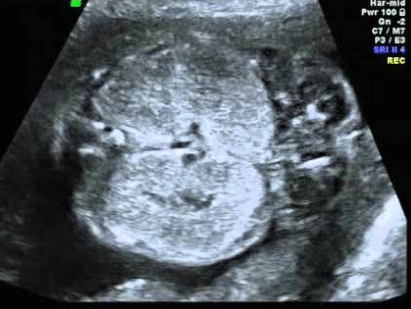

Holoprosencefalia A holoprosencefalia é uma anomalia caracterizada pela falta de divisão do lóbulo frontal do cérebro do embrião para formar Por: Dr Rafael Bruns 14/06/2020 4min